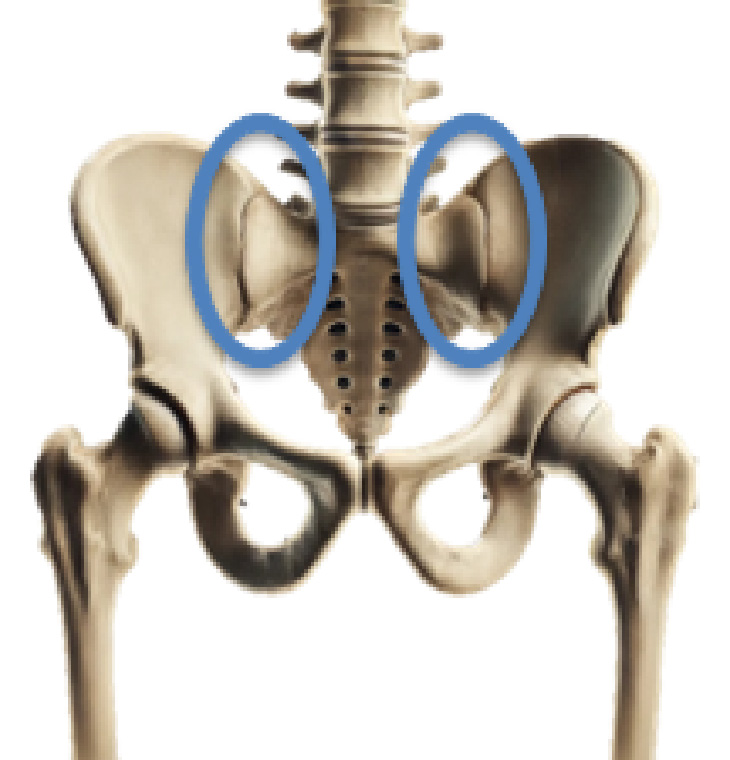

仙腸関節障害

仙腸関節障害とは

仙腸関節は後方を強靱な骨間仙腸靱帯および後仙腸靱帯で結合されており、可動域が小さく、その関節面は荷重線に対して垂直に近く、荷重に対して剪断力を生じやすい構造となっています。

仙腸関節障害は中腰での作業や不用意な動作、反復性の作業で繰り返しの負荷により骨盤周囲の筋の協調性に破綻が生じると関節に微小なずれが生じます。その結果、運動制限等の機能障害が起こり、疼痛が発生すると考えられています。

・腰の付け根付近(上前腸骨棘:PSIS)の痛み

上後腸骨棘(PSIS)付近にピンポイントで痛みが出現することが特徴です。